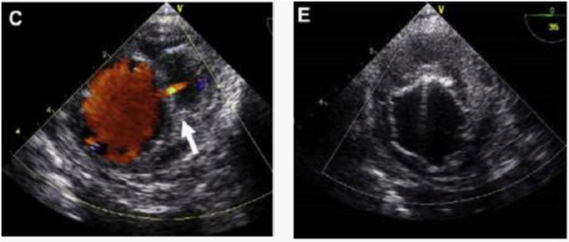

In contrast, Echo Doppler has been recognized as a good option to these techniques due to its low cost, easy implementation and interpretation and the absence of exposure to any type of radiation.26 This provides a better understanding of the endoleak formation mechanism and provides a more accurate analysis thereof, due to a collateral circulation. The origins of an endoleak may also be correctly identified. Compounded by the fact that it allows visualize blood flow in the aneurysm sac and its direction. This seems to be an excellent tool in the evaluation of high flow endoleaks within the aneurysmal sac. It is an imaging technique commonly used in vascular studies, being easy to perform, inexpensive, portable, secure and highly available. Its use for patients’ follow-up can reduce the biological hazards associated with CT angiography, since this frees the body of the individual to a substantial dose of ionizing radiation. The advantage of Doppler ultrasound in patients’ follow-up with aortic stent graft is that it allows a serial measurement over time of the residual diameter of the aorticaneurysm sac. Doppler ultrasound is more accurate than CT for the detection of problems associated with stent graft patency, their migration, kinking and stenosis. Provides physiological and anatomical information at the same time, unlike CT. The ability to quantify and compare serial images at a low cost without contrast and radiation, suggests that this technique should be the Gold Standard in the follow-up to TEVAR (Figures 5-9).20,24,27

Figure 9 (C) Image showing active bleeding from the aortic lumen into the hematoma (arrow). (E) TEVAR showing elimination of flow.30

Image protocol